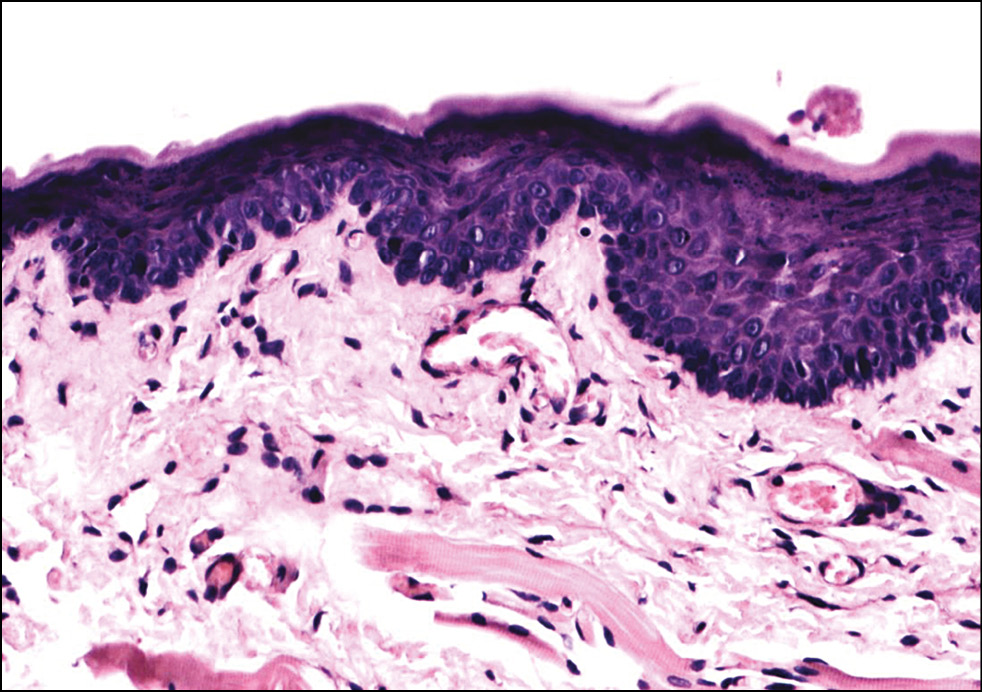

Рис. 8. Гистологическая картина кожи заушной области женщины через 20 дней после фотодинамической терапии. Окраска гематоксилином и эозином, x200.

Fig. 8. Histological picture of the skin behind the ear of women 20 days after photodynamic therapy. Hematoxylin and eosin staining, x200.

Подэтап 2А. Гистологическое исследование показало, что сразу после воздействия ФДТ (рис. 6) в коже обнаруживались единичные лейкоциты в толще эпидермиса и на его поверхности; ядра клеток эпидермиса и их цитоплазма на данном участке были набухшие, сосочки дермы несколько сглажены, рыхлая волокнистая соединительная ткань сосочкового слоя дермы отёчна. На третий день (рис. 7) после процедуры отмечено уменьшение количества набухших ядер в эпидермисе, заметны мелкоочаговые кровоизлияния в сетчатом слое дермы с перифокальной сосудистой реакцией и слабовыраженным отёком сетчатого слоя дермы. Спустя 20 дней (рис. 8) после воздействия заметна умеренная пролиферация клеток эпидермиса и дермы. Отмечается уплотнение коллагеновых волокон сетчатой дермы. Патологических изменений в эпидермисе, дерме, придатках кожи не обнаружено.

Таким образом, воздействие на кожу человека длиной волны 660 нм в течение 30 мин с использованием фотосенсибилизатора Сферометаллохлорина™ является безопасным и не приводит к развитию патологических реакций.

По данным гистологического исследования, воздействие излучением 660 нм на слизистую оболочку полости рта крысы не вызывает каких-либо отклонений от нормы; при воздействии излучением 660 нм с использованием фотосенсибилизатора на кожу заушной области женщин появляются небольшая отёчность и набухание ядер эпидермиса, которые полностью разрешаются через 20 дней; кроме того, зафиксировано утолщение коллагеновых волокон. Это позволяет сделать вывод о безопасности данной процедуры.